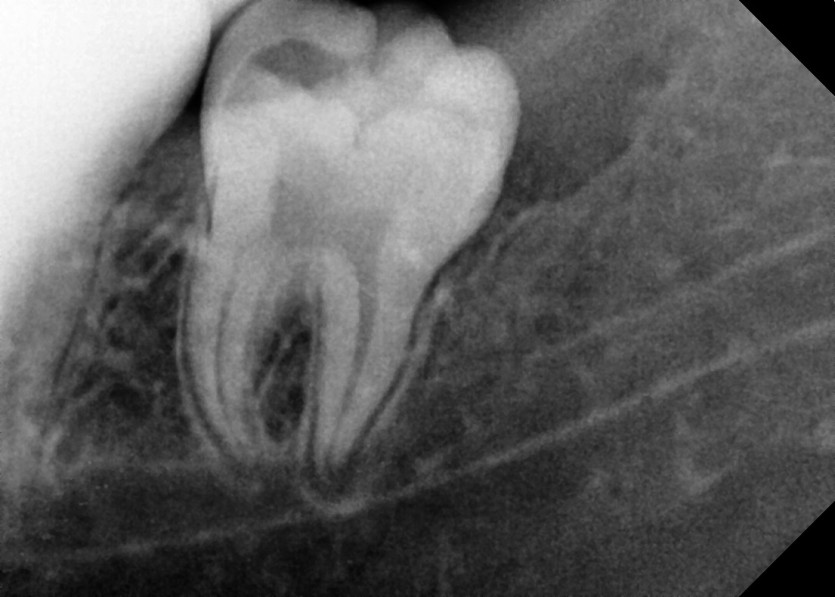

#38,48 사랑니 발치

구강 외과 전문의가 당일 발치했습니다.